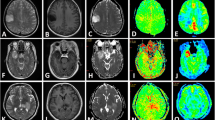

Previous studies have shown that increased levels of free (mobile) lipids are associated with higher grades in brain glioma. Magnetic resonance spectroscopy (MRS) is a noninvasive test approved as a noninvasive modality for assessing lipid concentration and tumor grade [10, 11]. Chemical shift imaging is a gradient-echo (GRE) MRI technique in which in-phase and opposed-phase (IOP) sequences are used clinically to spot lipids in renal angiomyolipoma [12], adrenal adenoma [13], bone marrow involvement [14], and whole-body fat quantification [15]. It could also be useful for detecting lipids in brain gliomas [16]. Elevated levels of HGG lipids may indicate greater loss of signal in the opposed-phase sequences [8, 17, 18]. The advantages of chemical shift IOP sequences are the shorter acquisition time, non-sensitivity to adjacent bone artifacts, wide applicability in MRI devices, general evaluation of the abundance of lipids, and no need for high-priced software applications and expertise [11, 19].

An expert radiologist examined the in-phase and opposed-phase images. Three 20–30-mm2 oval regions of interest (ROIs) were placed manually in the solid component in the in-phase and opposed-phase images, and the average signal intensity (SI) values were determined. The ROI was taken from the same solid area from which the MRS sequence was obtained. The solid part of the tumor is defined as the part of the tumor that is isointense on T1-weighted (T1W) images and presents an iso- to hyperintense signal on T2-weighted (T2W) images. The same “solid component” was used on both SVS and IOP imaging analyses. Based on the presence of the decreased SI area in the opposed-phase sequences by visual evaluation, we found the most suitable location for the ROI. The same ROIs were then used consistently across both sequences (Fig. 2).

Energy production in the brain occurs solely through the glucose mechanism, and the presence of lactate is associated with impaired normal brain mechanisms [21]. In this case, the accumulation of lactate in the brain is due to O2 deficiency (ischemic changes), increased glycolysis [22], or necrosis [23], which is observed in all tumor grades. Elevated lactate concentrations can be seen in both benign and malignant tumors [23] but the combined lipid-lactate peak is associated with HGG [24]. While lipids are normally found in cell membranes and myelin sheaths, damage and necrosis in high-grade brain tumors cause them to convert to mobile lipids [25]. The distinct lipid peak in MRS is associated with glioblastoma (grade 4; [24]). The presence of these two peaks has been suggested in several studies to differentiate between low-grade and high-grade brain gliomas. In our study, we found a statistically significant difference between SLR in tumors and the presence of these two elements. In contrast to MRS, the IOP can localize the abnormality and receive signals from anatomically defined regions. This is an important difference in the brain because most brain abnormalities are focal and the layer of cranial fat that surrounds the brain contains significant amounts of the same compounds found in the abnormalities.